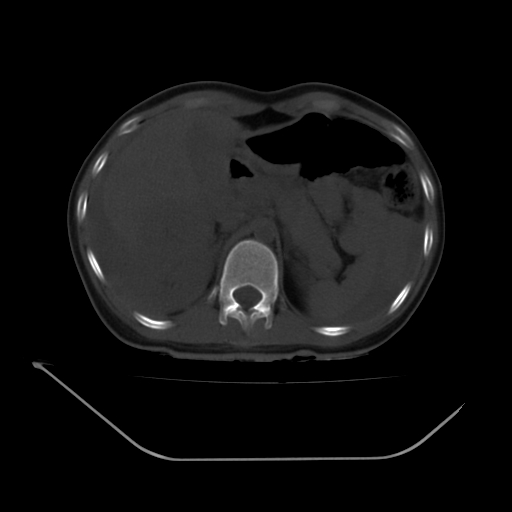

以下是引用liuyue在2008-7-19 13:02:00的发言:[br]1.肝右叶后下段及右肾挫裂伤伴腹腔积血。[br]2.右侧多发性肋骨骨折、横突骨折、右髂骨骨折伴周围软组织挫伤。[br]3.右侧腰大肌肿胀,并可见低密度影,如为气体,则肠道挫裂伤待除外。

以下是引用zhengfaming在2008-7-19 14:42:00的发言:[br]1.肝右叶后下段及右肾挫裂伤伴腹腔积血。脾脏挫裂伤待排[br]2.右侧多发性肋骨骨折、横突骨折、右髂骨骨折伴周围软组织挫伤。[br]3.右侧腰大肌肿胀,并可见低密度影,如为气体,则肠道挫裂伤待除外

以下是引用道哥在2008-7-19 16:52:00的发言:[br]肝右叶后下段及右肾挫裂伤、脾破裂伴腹腔积血。[br]2.双侧多发性肋骨骨折、横突骨折、右髂骨骨折伴周围软组织挫伤。[br]3.右侧腰大肌肿胀,并可见低密度影,如为气体,则肠道挫裂伤待除外。